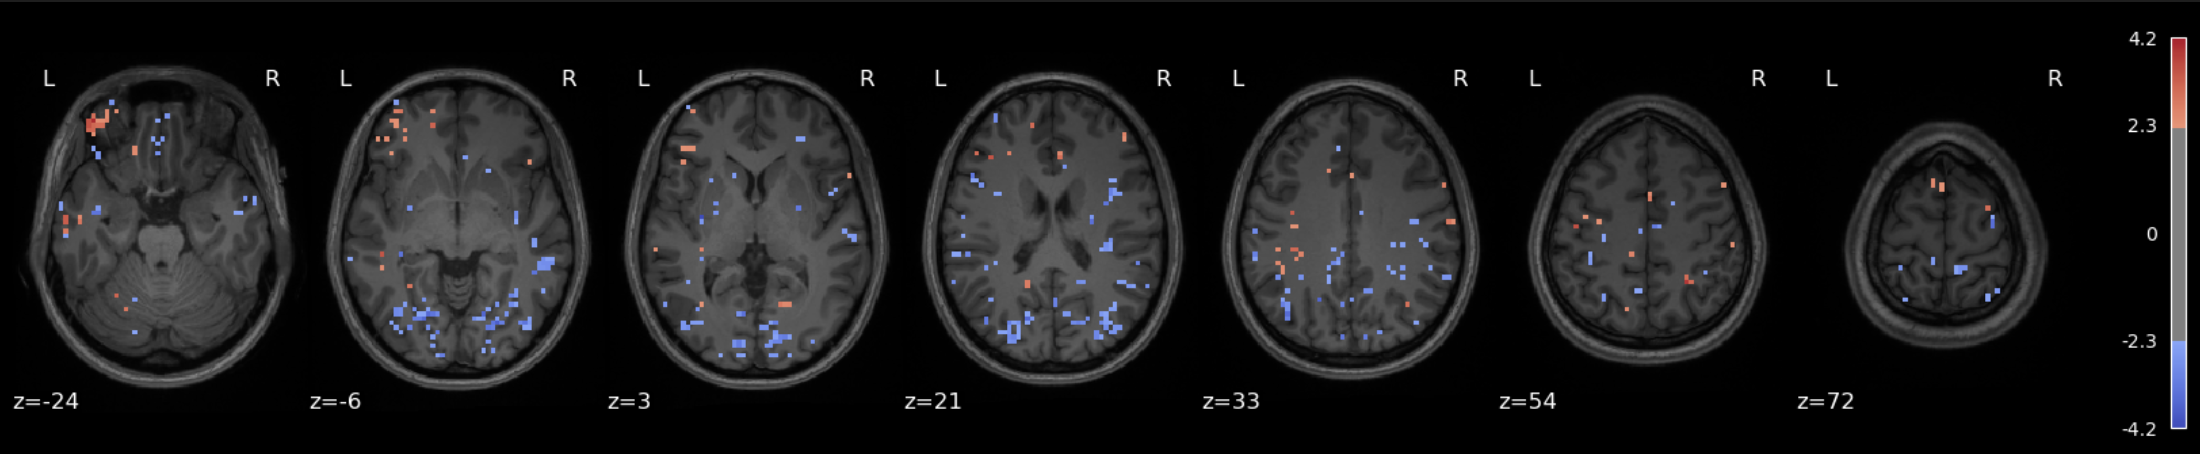

Approach 1 - GLM : Fear-related activation maps from 1 and 3 runs

The data for this participant includes 3 separate runs. Analyses were conducted on a sinlge run, as well as all three, in order to cultivate an intuition about what different amounts of data look like.

The question being asked here is: Which voxels show a linear relationship with subjective fear, irrespective of animal category?

As we’re working with fear, we’d hope to recover regions such as insula, thalamus, periacqueductal gray matter, locus cerulus, parabrachial nucleus and nucleus of solitary tract, medial frontal gyrus, anterior cingulate, amygdala and hippocampus, hypothalamus and maybe some ventromedial or dorsolateral prefrontal cortex.

One run

Three runs

See the Jupyter book for a deeper interpretation of these results, including both anatomical (Harvard-Oxford) and network-based (Schaefer) atlases, but suffice it to say that we were not able to recover fear-related subcortical regions, but some associative/integrative prefrontal regions are present.